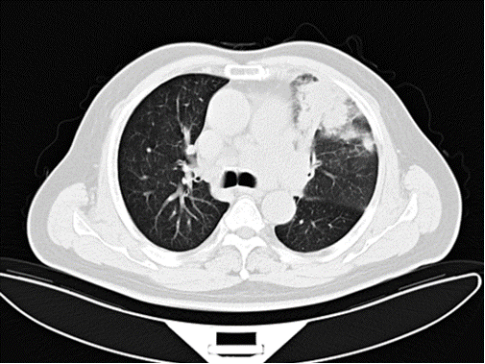

2019.08.23门诊胸部CT平扫:

1.左肺上叶斑片结节灶伴纵隔肺门淋巴结多发增大,恶性可能,建议进一步检查。

2.左肺下叶小结节,建议随访。

3.左侧胸腔少量积液。

4.心包积液。